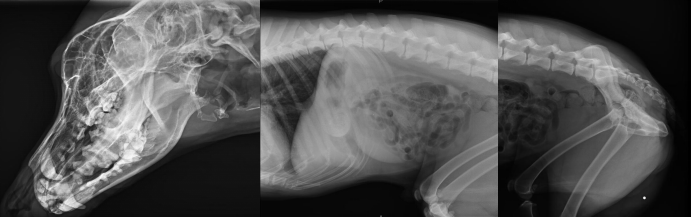

不管是人還是動(dòng)物,有一項(xiàng)檢查是非常常見的,就是X光拍片檢查,X光檢查是傳統(tǒng)的影像學(xué)檢查手段,它是應(yīng)用較早、普遍,價(jià)格也相對(duì)便宜。主要用于一些疾病的初步檢查,便于發(fā)現(xiàn)較明顯病變的組織和結(jié)構(gòu),是疾病初篩優(yōu)選的檢查方式。那么,一般寵物拍X光片和人拍X光片有什么不同點(diǎn),參數(shù)選擇一樣嗎?